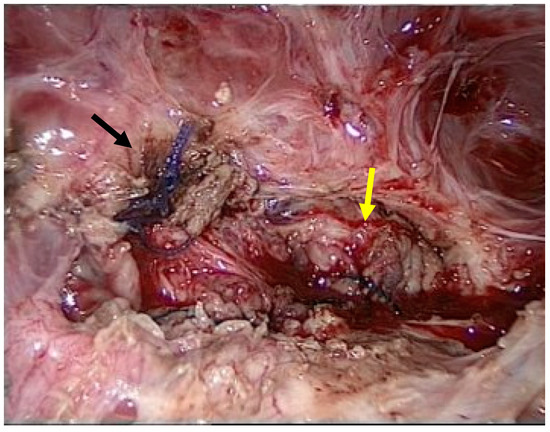

Adhesiolysis revealed a fistula between the urinary bladder and the uterus. The presence of sutures from a previous caesarean section most likely caused this abnormal communication. The abnormal tract between the two organs was removed using partial cystectomy, cystography, and partial myomectomy. Reconstruction was performed using a multilayer technique (Figure 3).

Figure 3.

Multiple layers of sutures of the vesico urinary (black arrow) and uterus (yellow arrow).